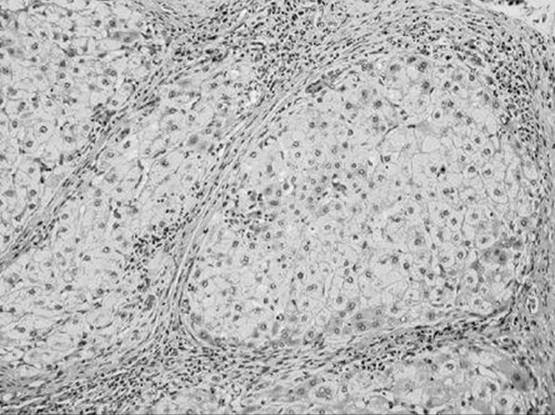

What liver condition is being demonstrated in the figure below? In this condition, what type of collagen is deposited to an excessive degree and what cell is its source?

Figure 51-1

Cirrhosis. Collagen of types I and III produced by the Ito cell. The Ito cell functions as a storage vehicle, metabolizes vitamin A, and aids in the production of collagen.